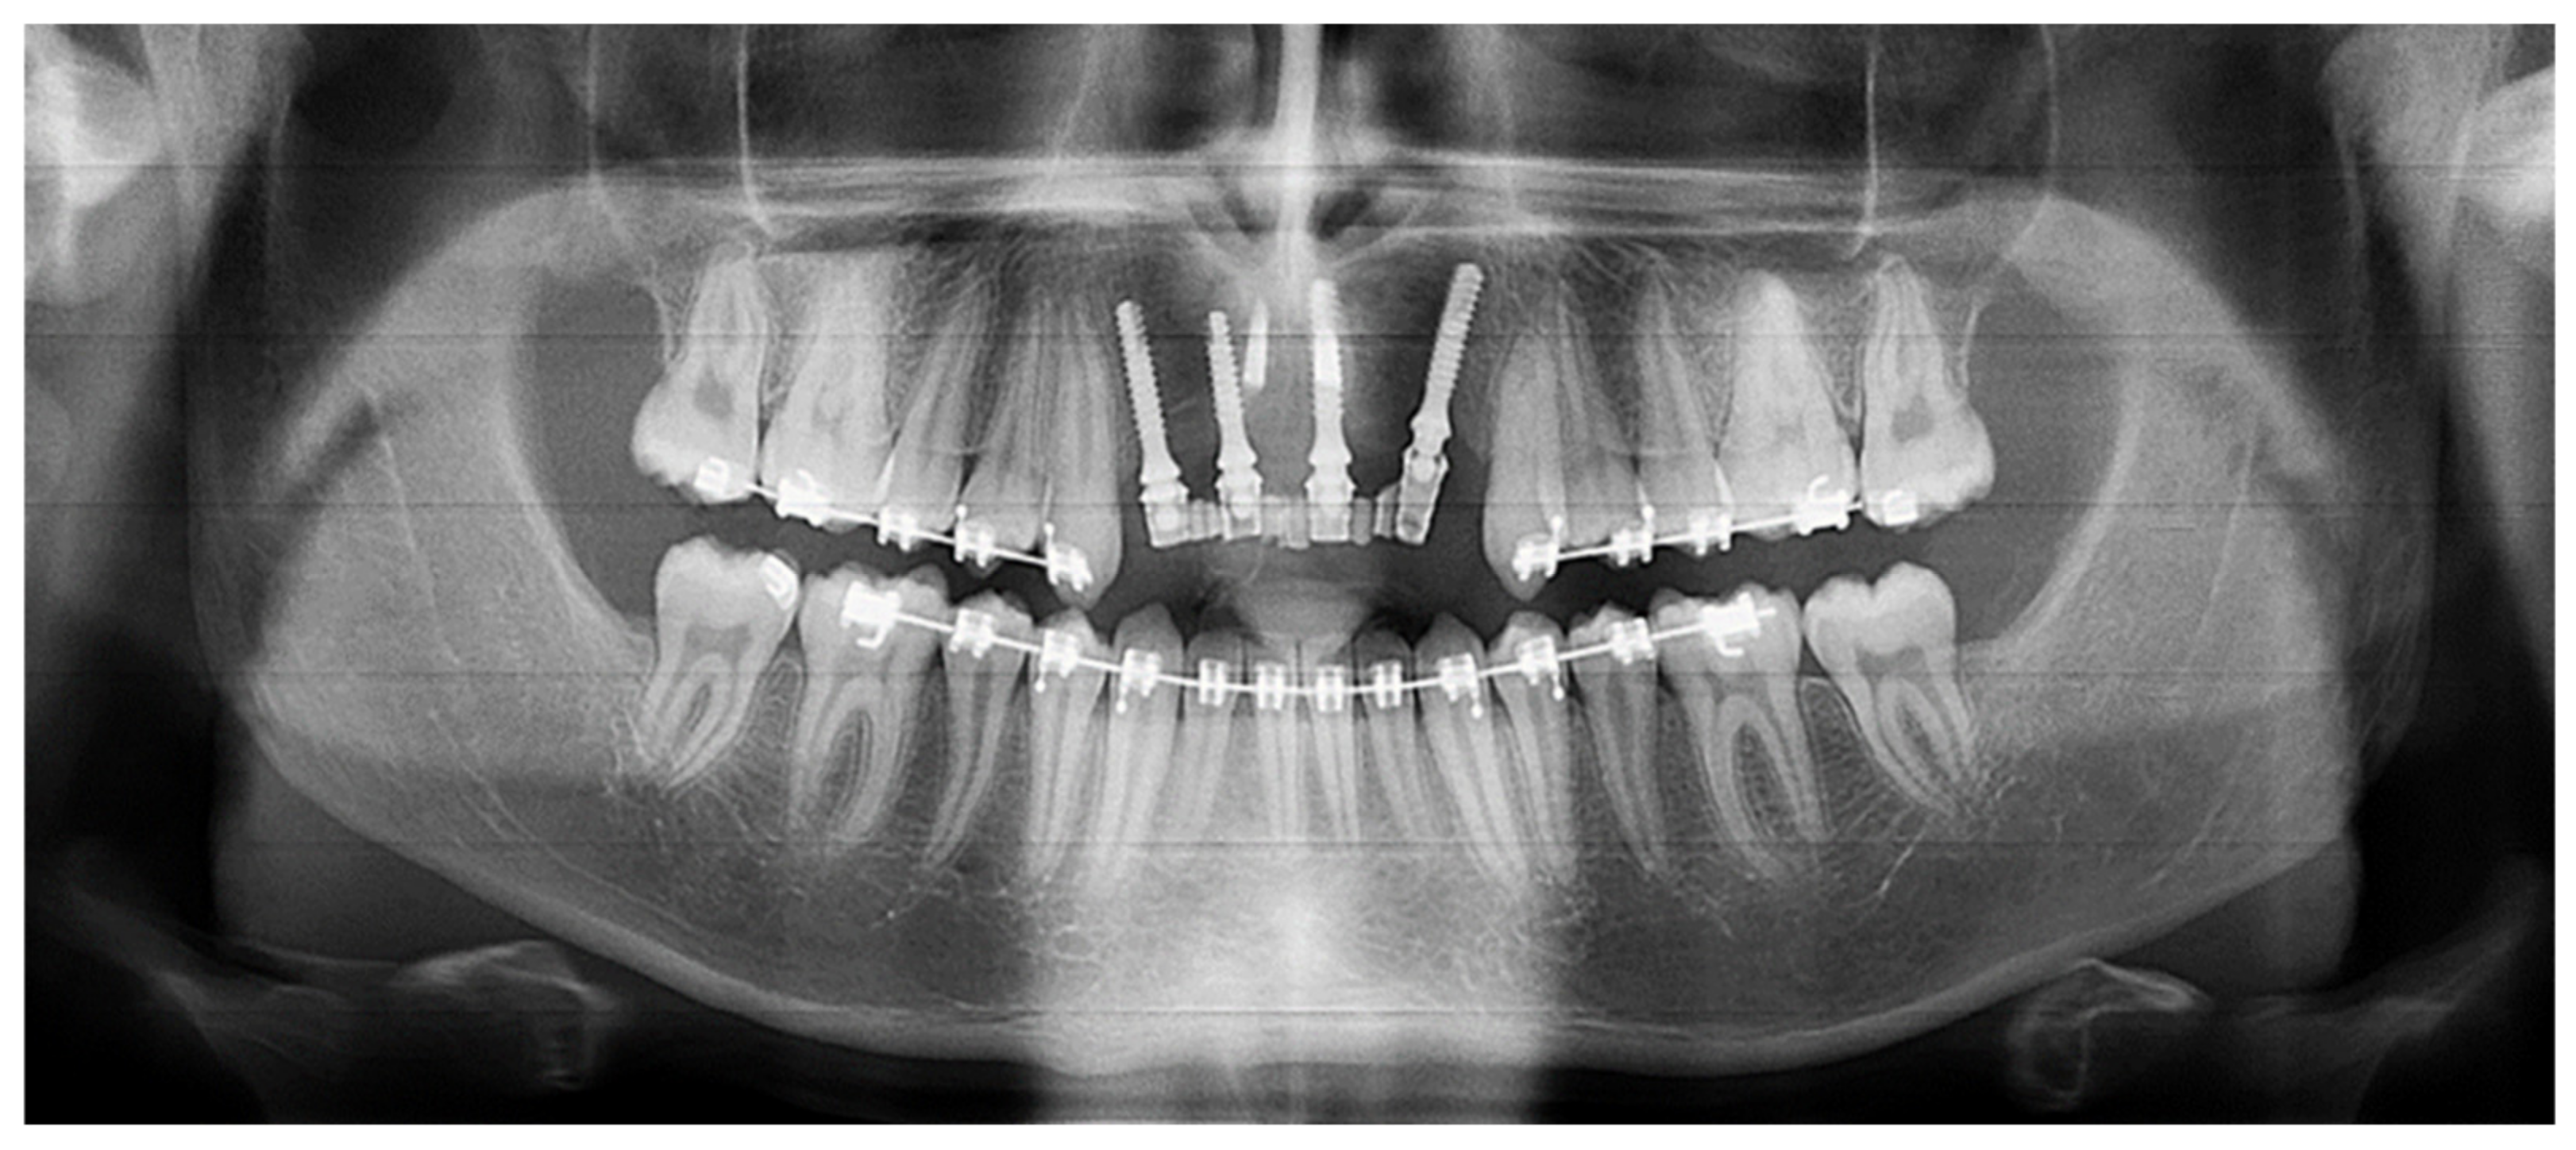

| May 2019: Orthodontic treatment for skeletal class II | Avulsion | |||

| Maintaining space for future implant replacement with resin crown temporization on the orthodontic arch | ||||

| Figure 8 | ||||

| Summer 2019 | Two infectious episodes despite an endodontic re-treatment | |||

| January 2020 | Avulsion | |||